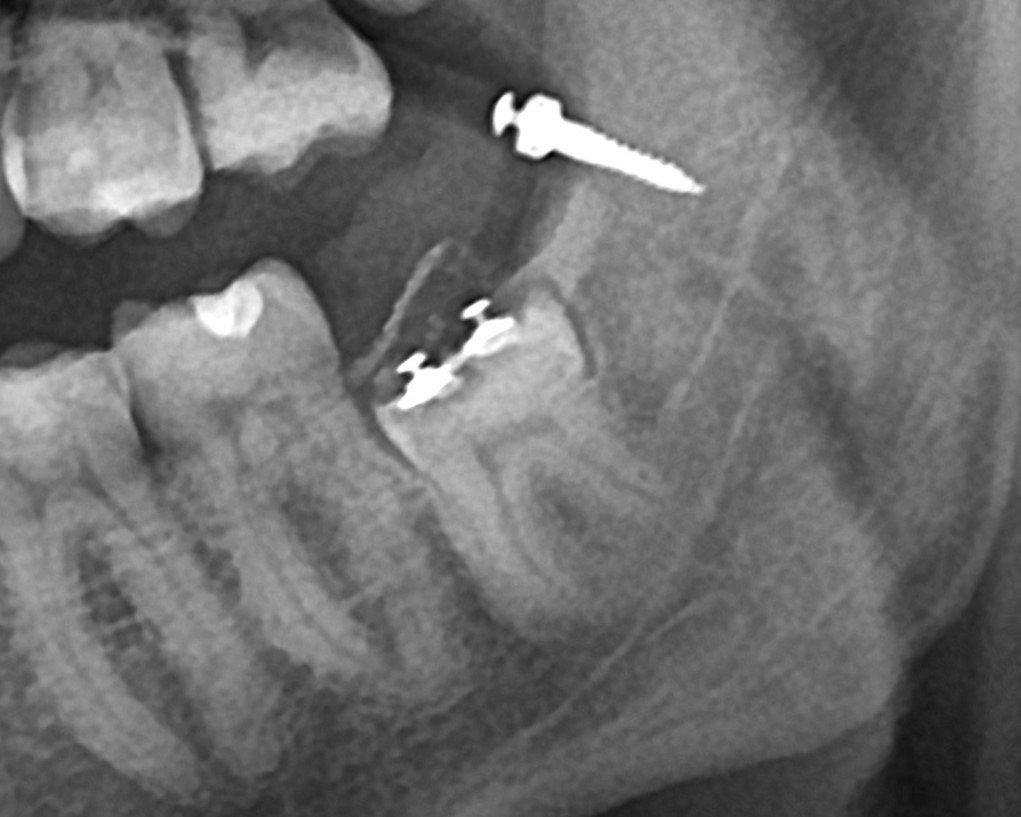

Установлен ортодонтический минивинт и три кнопки

послеоперационная ОПТГ

По данным ортопантомограммы (ОПТГ), проведенной через 7 недель после начала лечения, отмечалось недостаточное перемещение зуба.

ОПТГ через 7 недель. Уже заметен контур корня в области апекса.

Через 11 недель на ОПТГ наблюдалось незначительное, но прогрессирующее перемещение зуба.

ОПТГ через 0 , 7 , 11 недель. Заметна динамика.

К 14-й неделе лечения на ОПТГ было зафиксировано значительное  смещение  зуба, достаточное для его удаления.

ОПТГ на 14 неделе